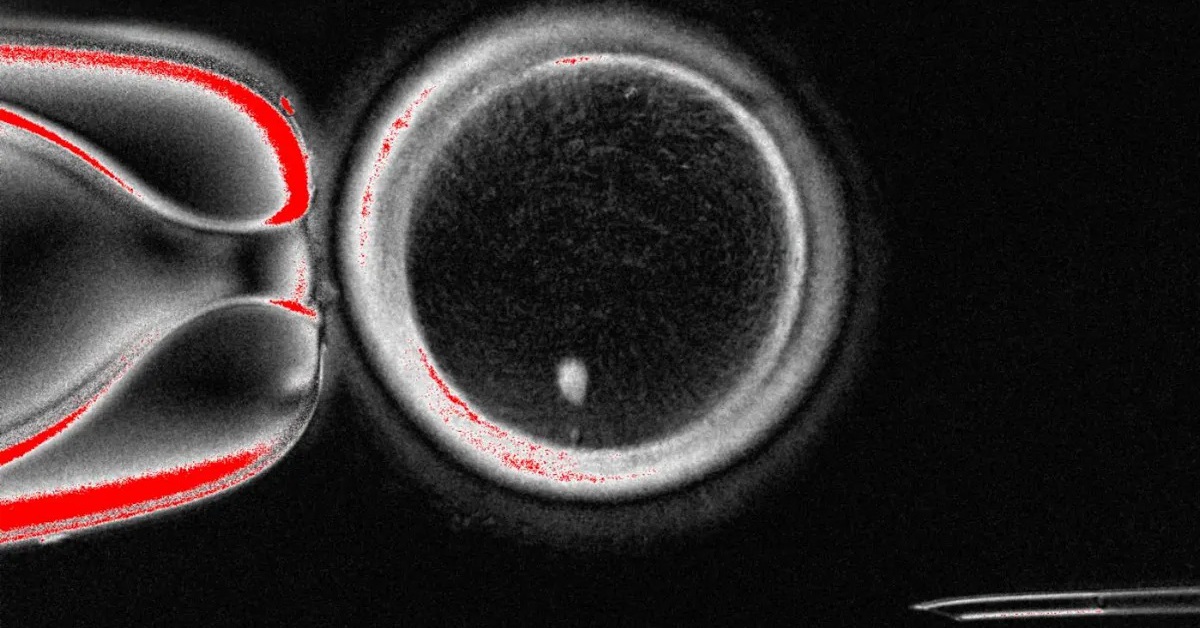

Trong nghiên cứu mới, do các nhà nghiên cứu tại Đại học Khoa học và Sức khỏe Oregon (Mỹ) dẫn đầu, nhân của tế bào da đã được cấy vào trứng hiến tặng đã loại bỏ nhân gốc.

Sau đó nhóm nghiên cứu kích thích các tế bào trứng để chúng trải qua quá trình gọi là "mitomeiosis".

Mặc dù tương tự quá trình nguyên phân (mitosis) - quá trình phân chia tế bào tự nhiên để tạo ra hai bản sao giống tế bào mẹ (46 nhiễm sắc thể), "mitomeiosis" có những điểm khác biệt quan trọng, dẫn đến việc một bộ nhiễm sắc thể bị loại bỏ, do đó tế bào con được tạo thành chỉ chứa 23 nhiễm sắc thể.

Tổng cộng, nhóm đã tạo được 82 tế bào trứng hoạt động bình thường từ quá trình này. Sau đó nhóm cho chúng thụ tinh với tinh trùng trong phòng thí nghiệm. Trong số này, có khoảng 9% phát triển thành phôi nang, giai đoạn đầu của quá trình phát triển phôi, sau sáu ngày.